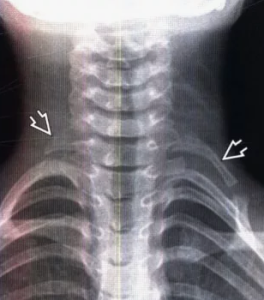

Рис. 2 Рентгенограмма пациента с ДШР справа и РШР слева

Второй по частоте причиной компрессии СНП являлось шейное ребро. У данной группы пациентов чаще отмечались тромбо-эмболические осложнения, при других формах СГВ. Гипотрофия мышц кисти (thenar и hypothenar) была характерным осложнением для этого синдрома и встречалась у четверти наблюдавшихся больных. Позиционная ишемия отмечалась у всех 140 пациентов. В 11 наблюдениях имела место постоянная критическая ишемия кисти и пальцев в результате тромбоэмболических осложнений. Во всех случаях рентгенологически было подтверждено наличие ДШР, а у 10 пациентов процесс был двухсторонним. Эти пациенты чаще всего лечились у невропатологов по поводу остеохондроза шейного отдела позвоночника.